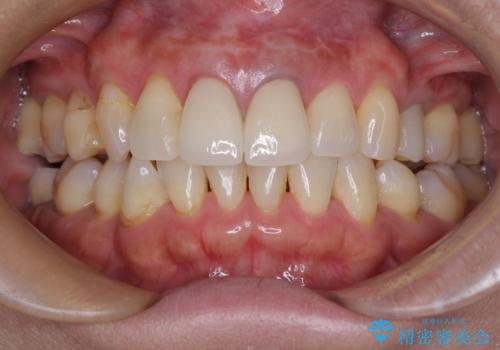

まずは審美的な仮歯を装着し、根管治療を行った後にオールセラミッククラウンにて補綴治療を行うこととしました。

根管治療後に痛みは軽減しましたが、僅かな痛みが続くとのことで、レントゲン写真では病変は認められなかったものの、歯根端切除を行うこととしました。処置後は痛みは全くなくなり、安心して補綴治療を行うことができました。